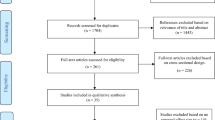

Based on this knolewdge, the objectives of the present study were: 1) to further explore, by using VBM in a large MS population, which GM regions subtend SDMT performance in MS, after controlling for the effect of focal WM lesions; 2) to assess, by usingVBM, which SDMT-correlated GM regions are atrophic in MS patient compared to HC; 3) to explore which of the SDMT-correlated and atrophic GM regions, identified by VBM and measured by FIRST, contributes to A-PS performance in MS patients.